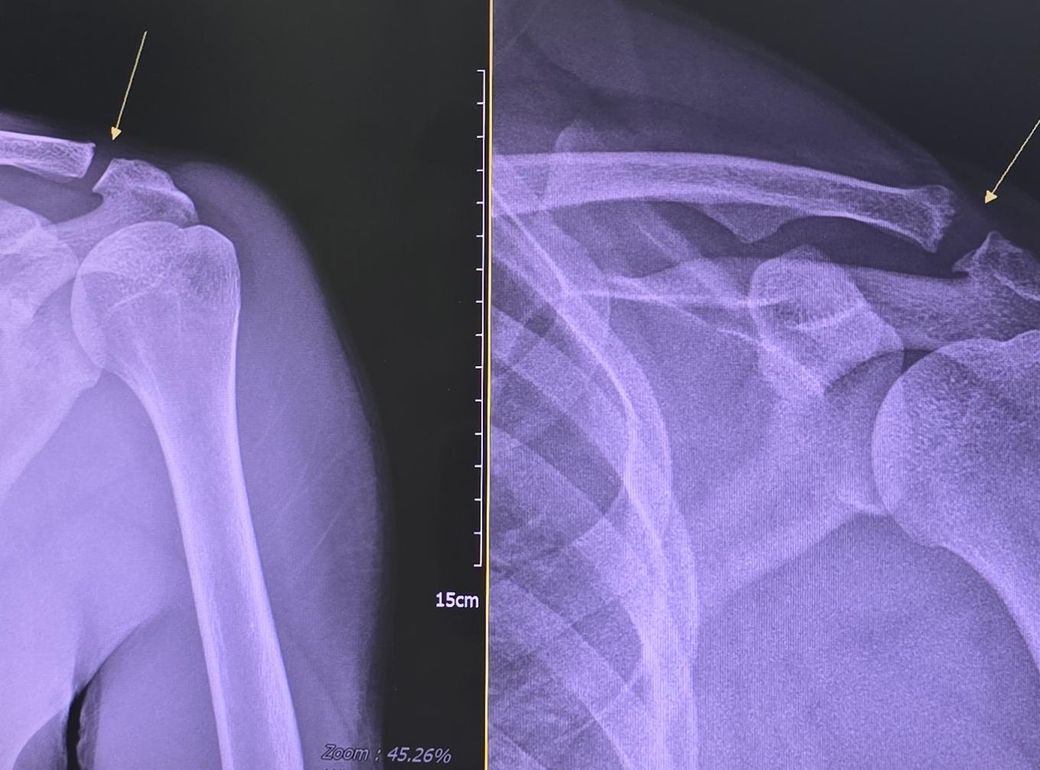

견봉쇄골관절 치료 가능한가요? 뜯긴 모양이 되어버렸어요

왼쪽 사진이 18년도에 찍은 사진입니다

정상일 때 사진이고요.

다행히도 자료가 있었네요.

오른쪽 사진이 최근 사진입니다

통증이 있어서 병원을 가서 촬영을 했는데

모양이 달라졌습니다.

사진상 "쇄골 말단(견봉쇄골 관절) 변형/부분 분리"가 진행된 모습으로 보이며, 예전처럼 "뼈 모양이 완전히 돌아오긴 어렵습니다."